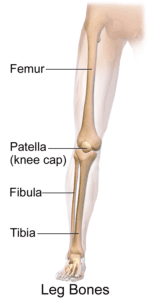

Patella (Kneecap) Fractures

Simple fractures or displacement of the kneecap can be immobilized with a cast for six or eight weeks. More complicated kneecap fractures require surgery (ORIF) to put the bones, muscles, and ligaments back in place. Knee fractures often lead to arthritis in the future.

More than 70 percent of car crash knee injuries are to the anterior cruciate ligament (ACL). When the ACL twists too forcefully in a car accident, it can become misshapen, or worse, torn.

An ACL strain can be painful, but when the force of a collision tears the ACL away from the knee joints, the pain is often excruciating and debilitating. Torn ligaments often require surgery followed by a long period of rehabilitation.

Your knee has two pads of cartilage that act as cushions between the thigh bone and shin bone. Each of these pads is called a meniscus. The impact from a car accident can tear or rupture the meniscus.

In more severe tears or rupturing of the meniscus, arthroscopic surgery (partial or total meniscectomy) is used to repair the meniscus and remove torn tissue debris. Recovery can take six to nine months of medical treatment and physical therapy.